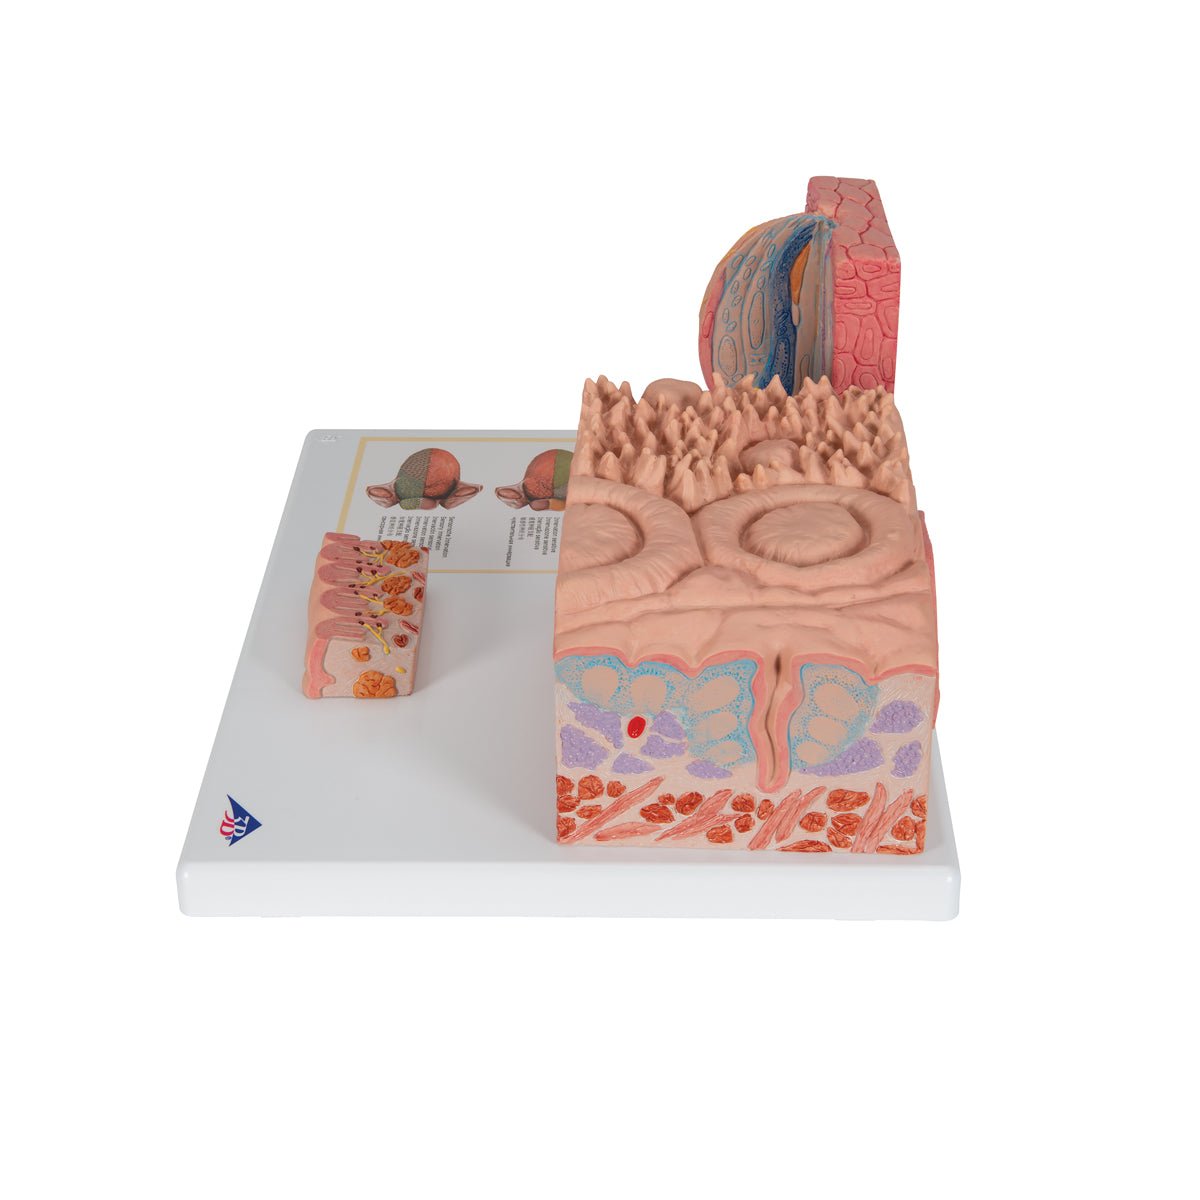

Salg af anatomiske modeller er det bærende element i eAnatomi, selvom vi også bruger mange ressourcer på at udvikle vores egne anatomiske materialer som fx plakater. Anatomiske modeller anvendes til forskellige formål og kan både vise afgrænset væv, organer samt organsystemer. Søger du en simpel model af knoglevæv eller måske en avanceret torso-model baseret på MRI teknologi, kan du finde det hele på eanatomi.com.